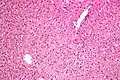

Micrograph showing ground glass hepatocytes. H&E stain.

In liver pathology, a ground glass hepatocyte, abbreviated GGH, is a liver parenchymal cell with a flat hazy and uniformly dull appearing cytoplasm on light microscopy. The cytoplasm's granular homogeneous eosinophilic staining is caused by the presence of HBsAg.

The appearance is classically associated with abundant hepatitis B antigen in the endoplasmic reticulum, but may also be drug-induced.[1][2] In the context of hepatitis B, GGHs are only seen in chronic infections, i.e. they are not seen in acute hepatitis B.